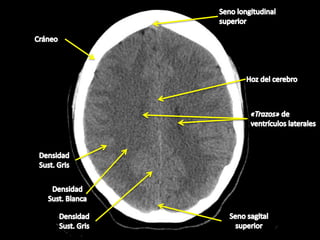

TAC de cráneo

SIRVE PARA DARLE UNA EXPLORACIÓN A EL CEREBRO

¿ Que detecta ?

sangraduras, lesiones cerebrales y fracturas del cráneo en pacientes con lesiones en la cabeza.

IMAGEN DE UN TAC